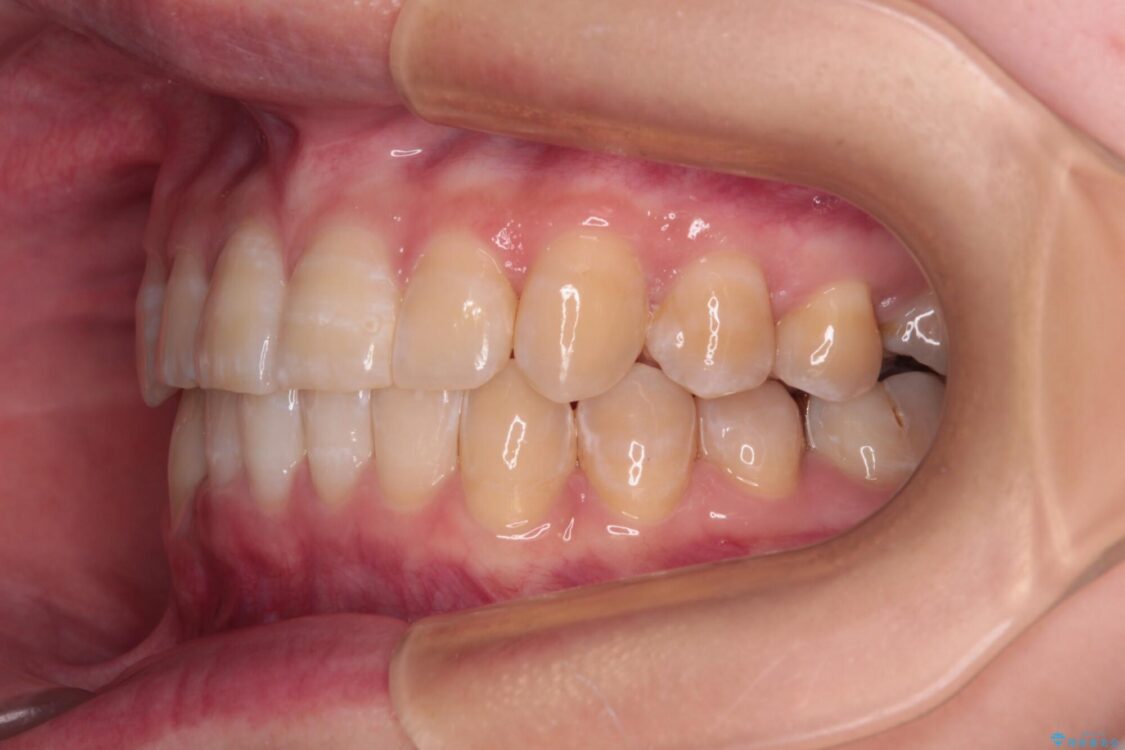

下顎の八重歯を気にして来院された患者様です。

下顎前歯にデコボコが集中していたため、顎間ゴムによる後方移動とIPR(歯と歯の間を削ること)により歯列を整えることとしました。

治療前、下顎前歯のデコボコが集中しており、奥歯の咬み合わせは、上顎に対して下顎が前方位にある状態でした。下顎の歯列を後方へ移動させる治療はインビザラインの得意とするところですので、1年程度で無事に治療を終えることができました。

• 【モニター】下顎前歯のデコボコをインビザラインできれいに 治療前画像